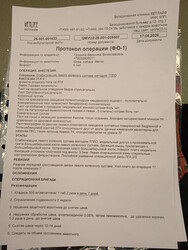

Всё оказалось совсем не так, как мы планировали. Мы поехали с бедром, аспасать пришлось колено.

Операция была на порванную коленную связку - левое колено. Это было выявлено

при дополнительном обследовании.

Само колено не ахти, разрушается. В него была введена половина дозы препарата

Noltrex (чек прилагается).

Правое бедро тоже разрушается, но доктор сказал его не трогать, если не

беспокоит. В него введена 2ая половина препарата.

Действие препарата от года до 5 лет. Можно им поддерживать. Контрольный рентген сделают, когда приедет в приют. Ограничение подвижности 3 нед, потом можно в вольер.

32 635 ₽ операция

17 250 ₽ анестезия

3 080 Р стационар

6 276 ₽ куплен Noltrex

1 840 Р лекарства по назначению хирурга

ИТОГО 61 081